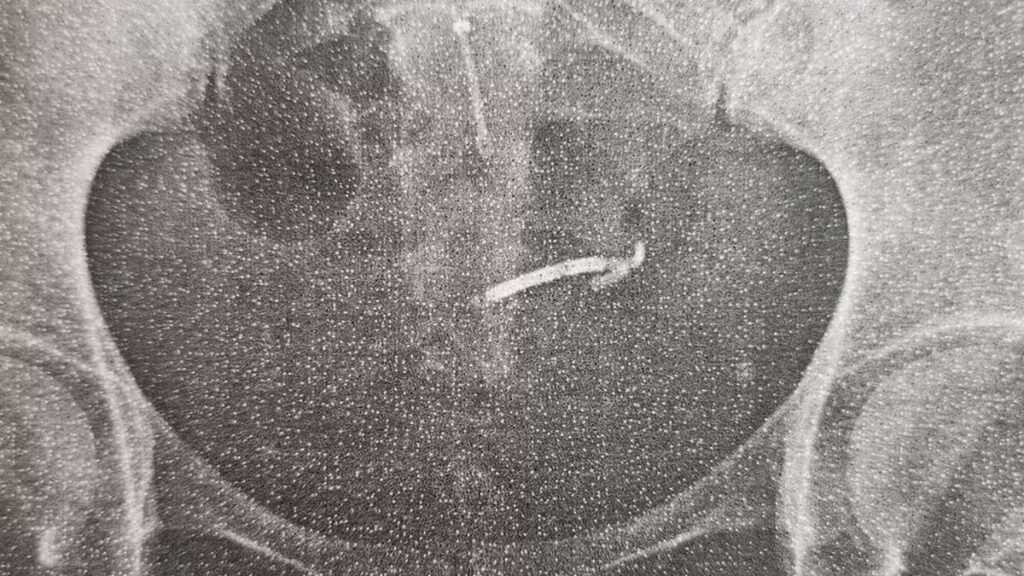

Mãe tem intestino perfurado após DIU ficar perdido no organismo por 3 anos

No entanto, no primeiro ultrassom após a descoberta da gravidez, Larah conta que que “o DIU não estava lá”. Mas isso, na época, não foi motivo de preocupação. “A gravidez foi tranquila. Fiz todos os exames. Foram mais de oito ultrassonografias e, em nenhuma delas, apareceu o DIU”, conta. “Tive o bebê por parto normal e, na época, o DIU não foi localizado. Então, os médicos disseram que, provavelmente, eu havia expelido”, conta. “Então, eu acreditei que realmente tinha expelido sem ver”, conta.